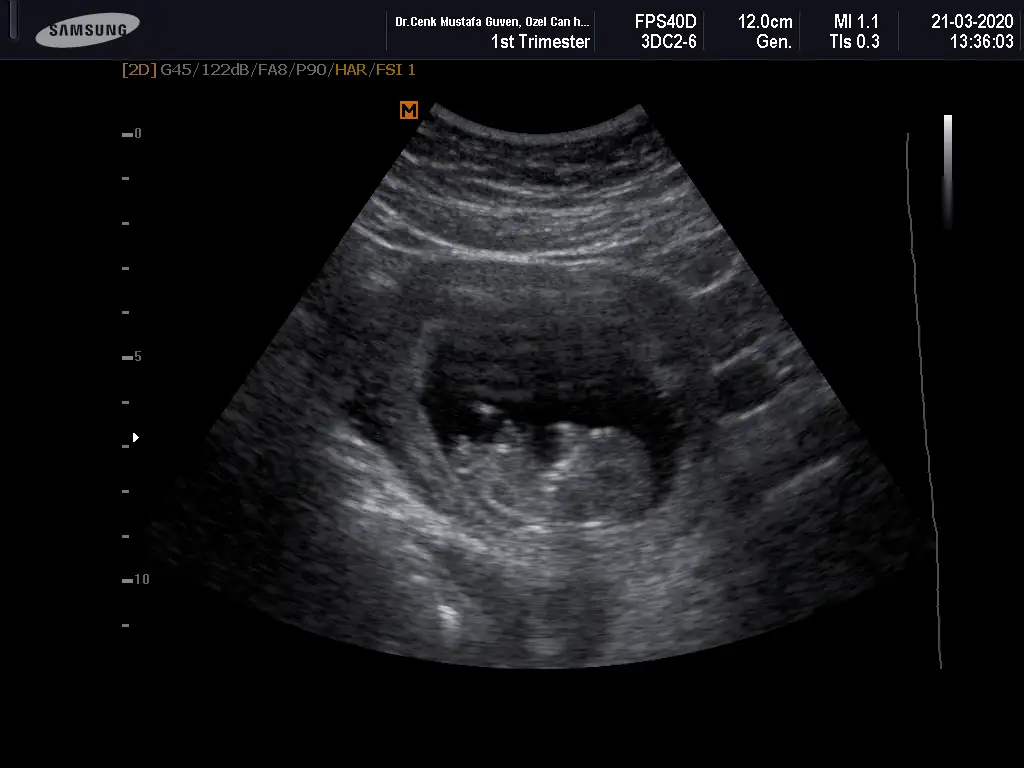

Merhaba yeni uyeyim elimde 7 haftalik karindan 10 haftalik alltan ulturason goruntusu var cinsiyet tahmini yapabilirmisiniz acaba şimdiden teşekkurler ilk resim 7 hafta karin son resim 10 haftta altan bakildi.

Keseye göre erkek ama tutmayabilir siz 11 12 13 haftaları paylaşın